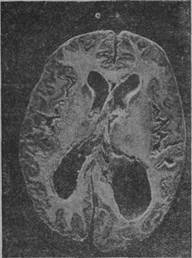

Детский и юношеский параличи с анатомической стороны представляют одну форму. Как известно, юношеская форма выделена Клустоном в 1877 г. Большинство наблюдений описано только с клинической стороны, но и анатомические особенности выяснены достаточно определенно. Первая из них, отмеченная Лафора и Альцгеймером,—это большая частота различных аномалий развития; именно здесь особенно часто наблюдаются двух- и трехъядерные клетки Пуркинье, неправильное расположение нервных клеток и гетеротопии серого вещества. Другая особенность—расширенна МОЗГОЕЫХ желудочков в гораздо более-значительных размерах, чем это наблюдается при параличе на почве приобретенного сифилиса (рис. 92).

Рис. 92. Случаи паралича на почве врожденного сифилиса. Расширение боковых желудочков.